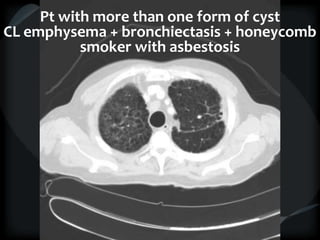

Pt with more than one form of cyst

CL emphysema + bronchiectasis + honeycomb

smoker with asbestosis